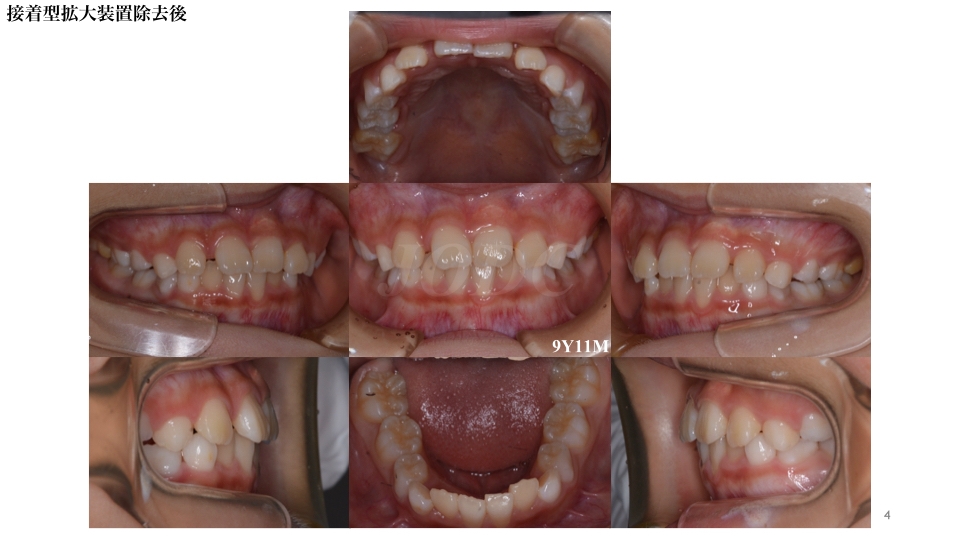

急速拡大装置により左側中切歯の反対咬合も改善され、開いていたスペースもキレイに閉じております。

第二大臼歯萌出まで経過観察を行い、成長終了後に抜歯を含めた再診断を行います。